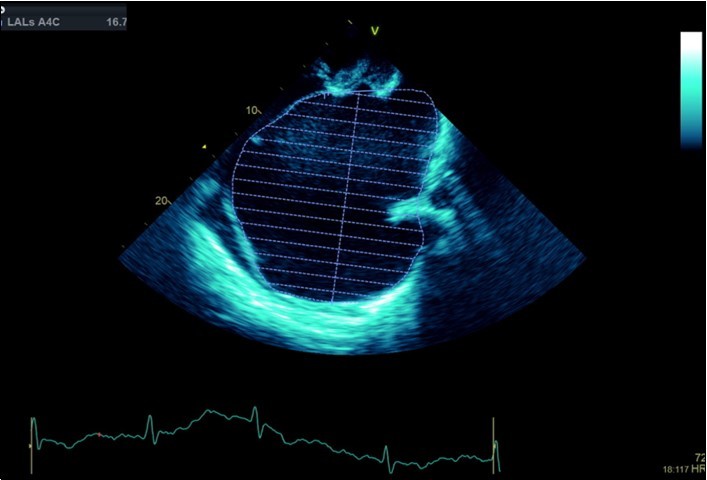

A dramatically dilated left atrium was seen on a TTE (see Figure 2a, Figure 2b, Figure 2c, and Figure 2d). Severe mitral stenosis with associated regurgitation was evident, with a mean gradient across the valve of 11mmHg and a hyperdynamic left ventricle. The left atrial volume measured by Simpson’s biplane method (see Figure 2c) was 2108mL, or 1548.5 ml/m2, based on height 1.55 metres and weight 44 Kg. Normal left atrial volume in a woman is 16 - 34 ml/m21. The computed tomography scan (CT) chest AP view (see Figure 3) is also shown.

Figure 2c.Transthoracic echocardiogram Apical 4C view. Left atrial size estimation by Simpson’s biplane method from apical 4C view.

Transthoracic echocardiogram Apical 4C view. Left atrial size estimation by Simpson’s biplane method from apical 4C view.